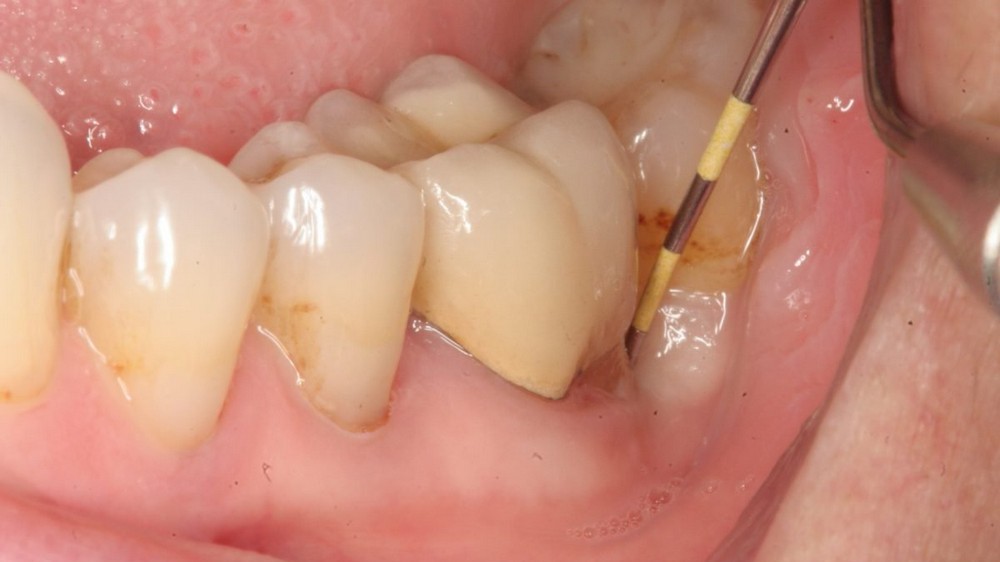

Cạo vôi răng, điều trị nha chu và dùng thuốc theo chỉ định nha sĩ

Cạo vôi răng định kỳ là bước cơ bản nhằm loại bỏ cao răng và mảng bám cứng đầu tích tụ lâu ngày. Sau quá trình này, các tổ chức quanh răng sẽ giảm thiểu viêm nhiễm đáng kể, giúp lợi hết sưng tấy và chảy máu. Để đạt hiệu quả tối đa, bạn nên khám nha khoa ít nhất 6 tháng một lần để duy trì tình trạng răng miệng lý tưởng.